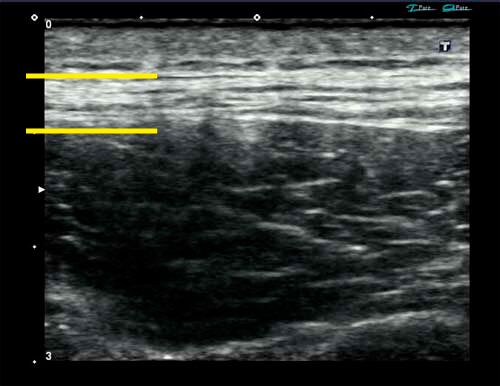

背部の凝りと痛み(2/X)|胸腰筋膜と太陽膀胱経